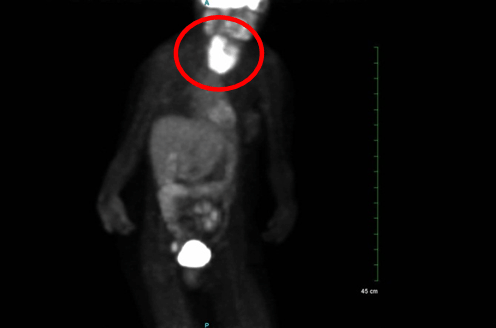

A 32-year-old female with a history of Hodgkin’s lymphoma presented with a two week history of thyromegaly. Hodgkin’s lymphoma was diagnosed at the age of 29 years and was treated with two cycles of ABVD (doxorubicin, bleomycin, vinblastine, and dacarbazine) chemotherapy and radiation therapy which was 2000 cGy in 10 fractions to the left lower cervical and supraclavicular nodal regions. One year after her diagnosis of lymphoma, she was considered to be in remission. She was also diagnosed with hypothyroidism with elevated anti-thyroid peroxidase antibody levels at the age of 29 years and treated with levothyroxine. At the age of 32 years , she developed thyromegaly causing dysphagia and hoarseness over a two-week interval. Physical examination revealed thyromegaly but no cervical lymphadenopathy. Due to her history of lymphoma positron emission tomography (PET) imaging was performed and demonstrated increased, diffuse fluorodeoxyglucose (FDG) uptake in the thyroid with right lobe being larger than the left (Figure 1). Ultrasound was also performed and showed thyromegaly especially on the right side but no thyroid nodules (Figure 2). Fine needle aspiration (FNA) of the right lobe was performed with flow cytometry of the needle washings (Figure 3). Flow cytometry of the needle washings did not show any clonal or aberrant populations of lymphocytes making lymphoma unlikely. Cytologic examination showed a background of lymphocytes and lymphoid stroma consistent with Hashimoto’s thyroiditis. Over the next two months the patient’s thyromegaly, dysphagia, and hoarseness gradually resolved. She continued to be treated with levothyroxine for her hypothyroidism related to Hashimoto’s thyroiditis.

Figure 2: Transverse ultrasound image demonstrating thyromegaly surrounding the trachea in the center of the image.The right lobe, left lobe, isthmus, and trachea have been labeled.